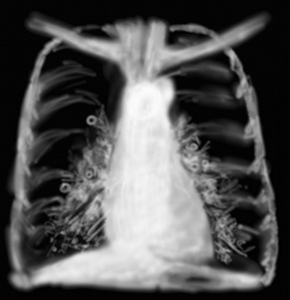

RP OAP avant traitement

RP OAP après traitement

Les opacités bilatérales alvéolaires groupées autour des hiles mais les débordant en cas de gravité très largement traduisent un oedème pulmonaire. L’OAP cardiogénique régresse quasi totalement sous diurétiques, vasodilatateurs et VNI et la radio post traitement montre souvent qu’une cardiomégalie et un liseré d’opacités paracardiaques bilatérales. C’est l’image qu’on voit aussi dans le choc cardiogénique.